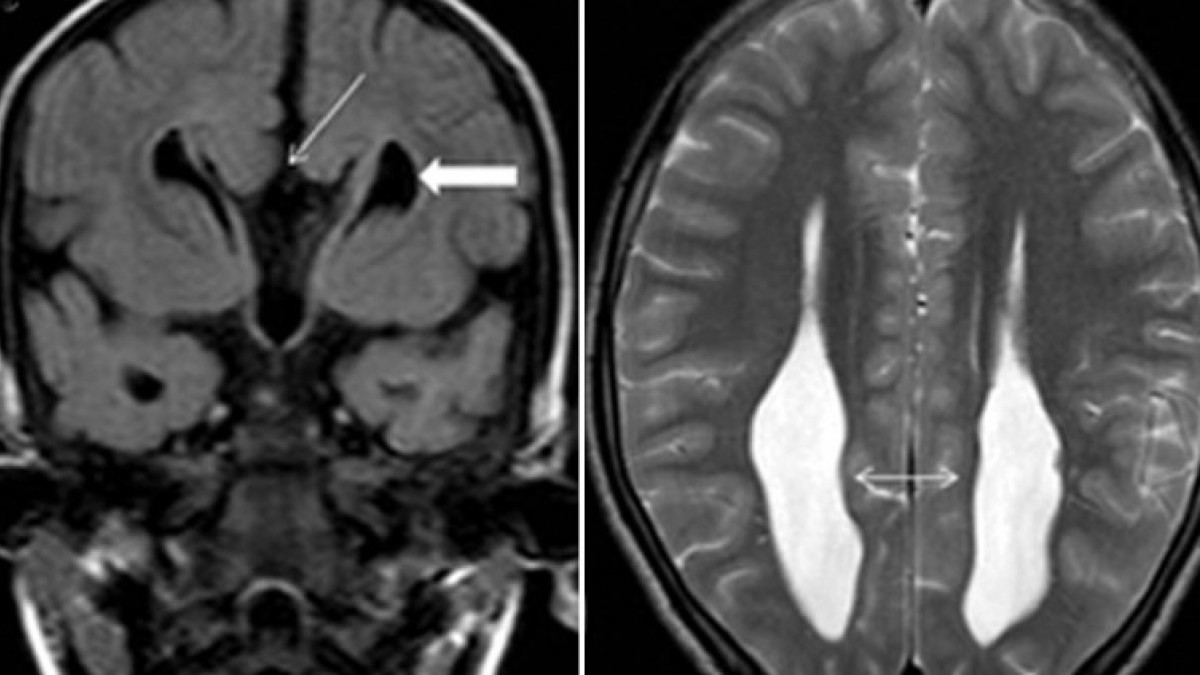

El virus de la encefalitis japonesa es la principal causa de encefalitis vírica en Asia. Se trata de un flavivirus transmitido por mosquitos que pertenece al mismo género que los virus del dengue, la fiebre amarilla y el Nilo Occidental.